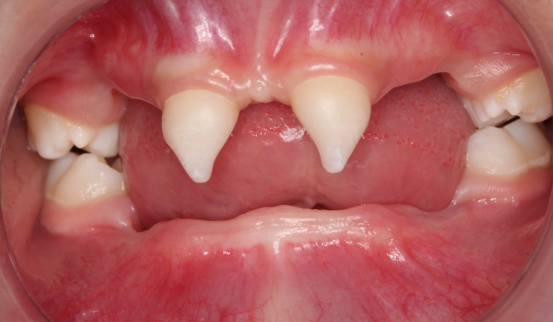

近年来,小艾电竞官方网站(后文简称小艾电竞 )在临床诊疗方面每年均有多个技术创新或突破。期间,副院长、口腔修复种植科主任医师王永曾带领团队完成多名外胚层发育不全患儿的可摘局部义齿及全口义齿修复,222日,更是为一位4岁患儿完成了罕见外胚层发育不全可摘局部义齿修复该患儿为目前口腔医院完成修复治疗年龄最小的患者

患者4岁,乳牙未正常萌出,上颌仅4下颌仅2颗乳牙,不能正常咀嚼,于2022年底在外地就诊多次无法修复,专程到口腔医院就诊。在后疫情时期,患者经王永门诊诊治后商讨出诊疗方案医院细心安排,于222由王永带领谭雯珈、姜炜鹏等医师,使用修复、正畸、修复工艺等多项技术,顺利完成了大面积乳牙缺失修复患儿现场进食效果良好,家长及患儿十分满意。

因其口腔表征为先天缺牙甚至无牙颌,且缺牙患儿口内余留牙往往表现为锥形牙、釉质发育不良、牙槽嵴发育不良等,可严重影响患儿的咀嚼功能及面部软硬组织生长发育。

(2) 牙弓较小,常规人工牙无法完成排牙;

(3) 牙体形态发育异常,常规卡环固位力差。